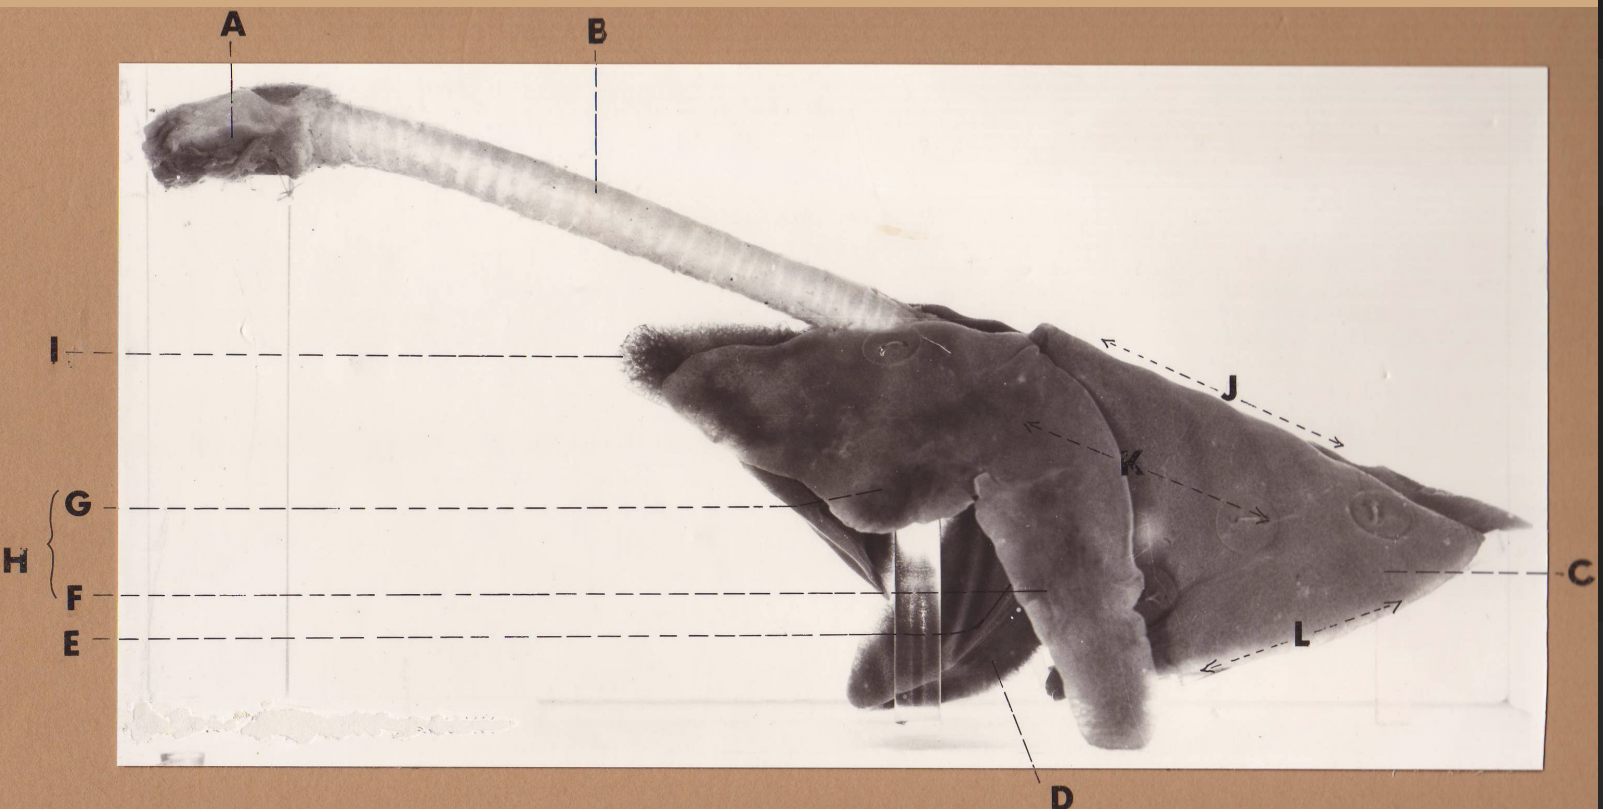

A

(cat larynx/trachea/lungs, L lateral)

larynx

B

(cat larynx/trachea/lungs, L lateral)

trachea

C

(cat larynx/trachea/lungs, L lateral)

caudal lobe

D

(cat larynx/trachea/lungs, L lateral)

middle lobe

E

(cat larynx/trachea/lungs, L lateral)

cardiac notch

F

(cat larynx/trachea/lungs, L lateral)

caudal segment

G

(cat larynx/trachea/lungs, L lateral)

cranial segment

H

(cat larynx/trachea/lungs, L lateral)

cranial lobe

I

(cat larynx/trachea/lungs, L lateral)

apex

J

(cat larynx/trachea/lungs, L lateral)

dorsal border

K

(cat larynx/trachea/lungs, L lateral)

costal surface

L

(cat larynx/trachea/lungs, L lateral)

basal border